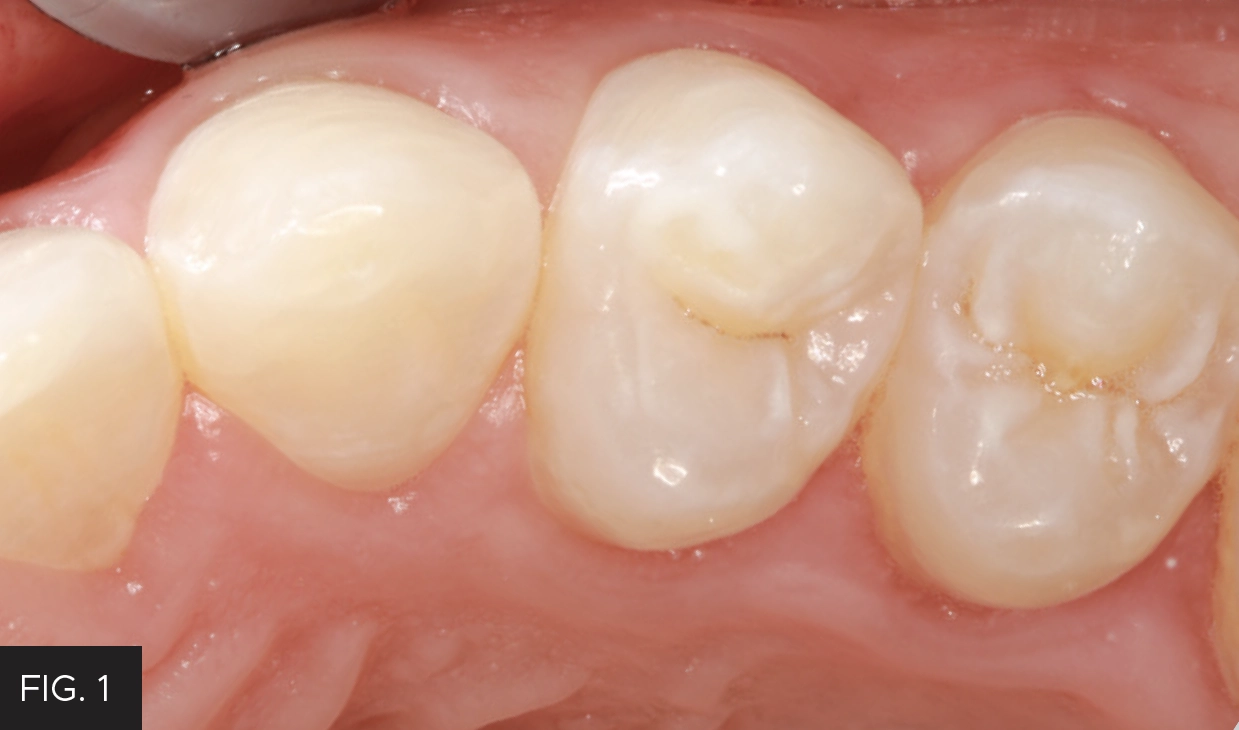

Evanesce™ Nano-Enhanced Universal Restorative ( Clinician’s Choice) in shade A3 was applied in 2mm increments utilizing the Compo-Ject™ (Clinician’s Choice) composite gun. Each layer was adapted to the preparation using the OptraSculpt® Instrument with ball modeling attachment (Ivoclar). The final layer was contoured with the Composite Ninja Instrument (Clinician’s Choice), as its unique angulated two-sided blade allows easy access to all areas of the tooth surface and then light-cured for 20 seconds. (FIG. 5)

Evanesce A3U composite (Clinician’s Choice) was sculpted and adapted to the preparation using a Composite Ninja (Clinician’s Choice). This versatile instrument has a thin 2-sided blade capable of reaching all surfaces of the tooth.